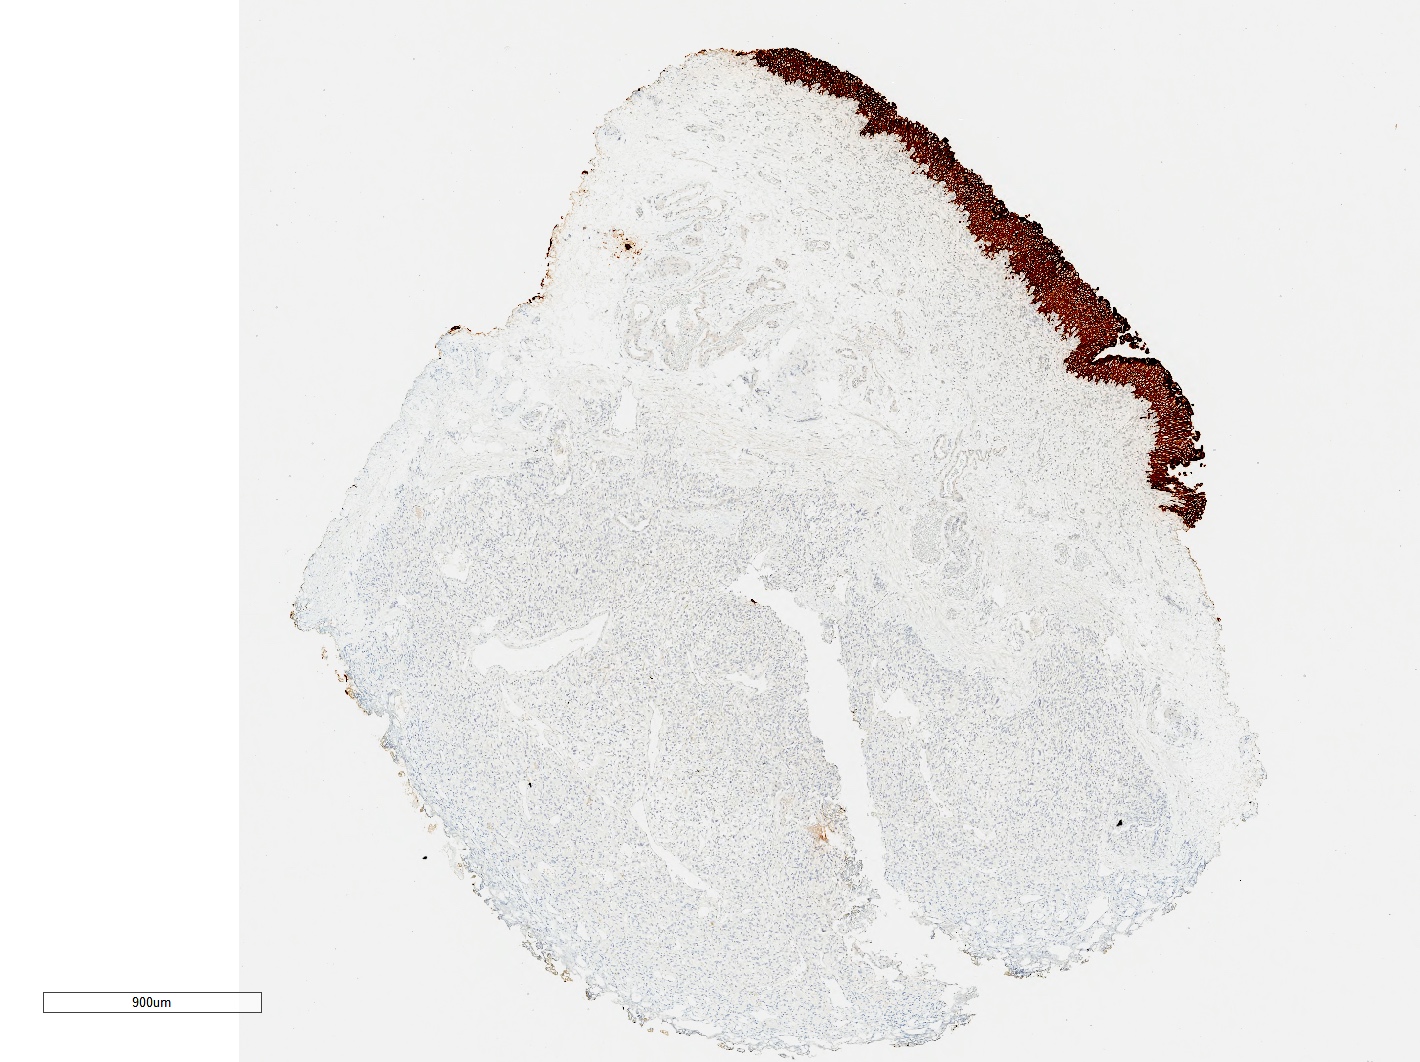

- SDHB germline mutation is the strongest genetic prognosticator of poor outcomes; SDHB immunohistochemistry is routinely used for its identification

- Modified GAPP: based on the same prognostic factors as GAPP with the addition of SDHB loss on IHC (PLoS One 2017;12:e0187398)

- COPPS (composite pheochromocytoma / paraganglioma prognostic score), with unfavorable factors being focal or confluent necrosis, PS100 loss, vascular invasion, SDHB loss, tumor size > 7 cm, capsular invasion, increased mitotic figures and MCM6 (minichromosome maintenance) > 30% (Virchows Arch 2019;474:721)

Microscopic (histologic) images

Contributed by Theodorus H. van der Kwast, M.D., Ph.D., Michelle R. Downes, M.D., Debra L. Zynger, M.D. and David Cohen, M.B.B.Ch., M.D.

- SDHB loss (absence of granular cytoplasmic labeling) if SDHB mutation

- SDHA loss (absence of strong diffuse granular cytoplasmic labeling) if SDHA mutation

- Paraganglioma, SDHB staining intact (see comment)

- Comment: The risk of malignancy in these lesions is estimated at 5 - 15% of cases. Malignant behavior cannot be predicted based on morphology alone and relies on the identification of metastases. Tumors associated with SDHB mutations (loss of SDHB staining) are reported to have an increased risk of metastases.

- Microscopic description: This specimen shows an unencapsulated, monomorphous population of round tumor cells in a nested / zellballen pattern with delicate vascular septa and intervening extravasated red blood cells. It predominantly involves the lamina propria of the bladder but in 1 tissue piece clearly involves muscularis propria. The tumor cells have abundant amphophilic cytoplasm and vesicular chromatin with occasional small nucleoli. There is no necrosis, diffuse growth pattern or vascular space invasion identified. The mitotic count is (maximally) 1/10 high power fields. Immunohistochemistry shows the tumor cells to be positive for GATA3 with strong and diffuse expression of synaptophysin and chromogranin, as well as retention of SDHB staining. The tumor cells are negative for AE1 / AE3, HMWK and p63. The Ki67 proliferation index is < 1%. S100 shows faint nuclear and cytoplasmic staining with occasional sustentacular cells identified.